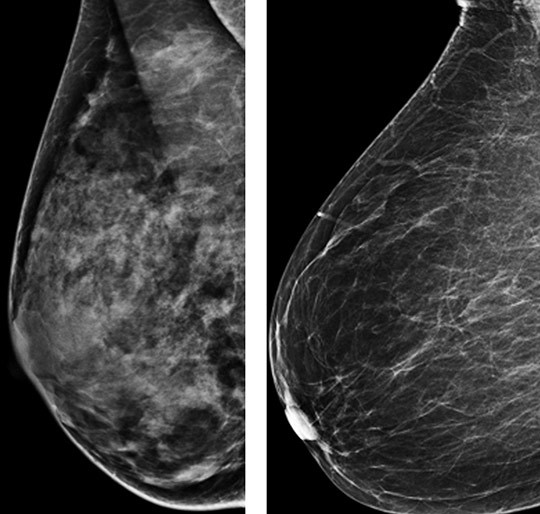

Illustrasjonsfoto: Ap/Scanpix

Høy mammografisk tetthet kan maskere svulster og redusere sensitiviteten ved mammografiscreening. Bruk av andre bildeundesøkelser i tillegg til mammografi er vist å øke deteksjonsraten. Hvordan brystkreftrisiko og mammografisk tetthet er assosiert med diagnose av infiltrerende brystkreft innen 12 måneder etter mammografi (intervallkreft), er nå undersøkt i en prospektiv kohortstudie i USA (1).